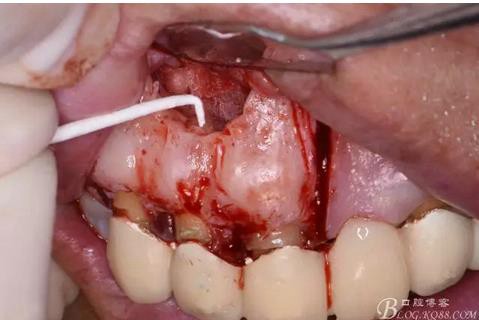

圖11.摘除囊壁后形成的骨腔

圖12.超生骨刀切除12根尖

圖13.根尖倒預(yù)備

圖14.吸潮紙尖干燥根管